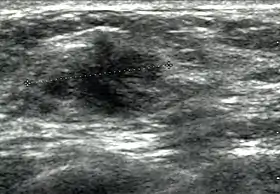

Breast ultrasound is a medical imaging technique that uses medical ultrasonography to perform imaging of the breast. It can be performed for either diagnostic or screening purposes[1] and can be used with or without a mammogram.[2] In particular, breast ultrasound may be useful for younger women who have denser fibrous breast tissue that may make mammograms more challenging to interpret.[3][4]

Elastography is a type of ultrasound examination that measures tissue stiffness and can be used to detect tumours.[7] Breast ultrasound is also used to perform fine-needle aspiration biopsy and ultrasound-guided fine-needle aspiration of breast abscesses.[8]